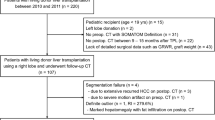

In this section, the feature extraction strategy is explained (“Feature extraction” section) as well as the classification model training (“Model training” section). We will explore both supervised (“Supervised approaches for patch classification” section) and semisupervised (“Semisupervised approach for image classification” section) classification approaches. The evaluation protocol, which includes materials, parameter setting, and performance measure definition, is explained in “Evaluation” section. The workflow of the proposed method for LT assessment is shown in Fig. 2.

In this study, we analyzed 40 RGB images, which refer to 40 different potential liver donors. HS was assessed with histopatological analysis performed after liver biopsy.

Biopsy was performed during procurement, taking surgical triangular hepatic samples up to 2 cm. One pathologist analyzed the histological sections. Steatosis was visually assessed based on the percentage of hepatocytes with intracellular large lipid droplets by using a semicontinuous scale [0:5:100%].

From the dataset, 20 livers referred to discarded grafts, as with a HS \(\ge 60\%\). The remaining 20 livers had a HS \(\le 20\%\) and were transplanted. Images were acquired with a smartphone RGB camera. Image size was \(1920\times 1072\) pixels. All the images were acquired with open-surgery view, as no laparascopic procurement is performed for cadaveric donors [14]. Challenges associated with the dataset included:

Visual samples of liver images are shown in Fig. 3.

From each image, liver manual segmentation was performed to separate the hepatic tissue from the background (Fig. 4). The manual segmentation of the liver images was performed with the help of the software MATLAB ®. The liver contour in each image was manually drawn by marking seed points along the lived edges, which were then connected with straight lines by the software.

The whole image was then divided in non-overlapping patches of size \(100\times 100\) pixels starting from the top-left image corner. We chose such patch size as image-patch size is usually of the order of magnitude of \(10^2 \times 10^2\) pixels (e.g., [32]). The most right part of the image, for which it was not possible to select full patches, was discarded. This did not represent a problem since the liver was always displayed at the center of the image. A patch was considered valid for our analysis if it overlapped with at least 90% of the liver mask.

To have the same number of patches from each patient, we first computed the minimum number of image patches that we could obtain among all images, which was 15. Then, we randomly extracted 15 patches from all the other images. As result, our patch dataset was composed of 300 patches extracted from transplanted liver and 300 from non-transplanted ones. Sample patches for transplanted and non-transplanted livers are shown in Fig. 5.